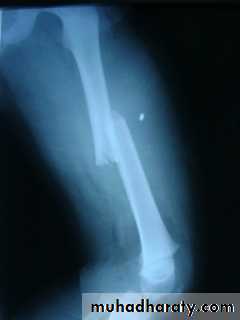

Femoral shaft fracture

This fracture occurs at any age, it is common especially in young adults, and usually results from a high energy injury, such as

( car accident , fall from height).

In elderly ,

it may be pathological fractureIn children think of child abuse.

Fracture may be

spiral,transverse, comminuted, pathological,

or compound.

Most fractures have some degrees of comminuation (small fragment, single large butter fly, extensive comminuation).

X-ray :

Shows the type of fractures, and displacement. The x-ray should include the hip and knee and x-ray of pelvis to avoid missing segmental fractures, knee injuries, fractures of neck of femur, dislocation of hip, fractures of acetabulum and pelvis.